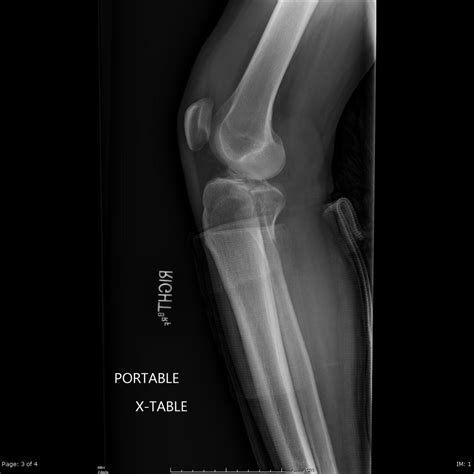

Because the tibial plateau is integral to stability, a fracture here is considered a serious injury. It not only damages the bone structure but can also affect the soft tissues, ligaments, and nerves surrounding the knee joint. Proper diagnosis using imaging techniques like X-rays or CT scans is critical to determine the severity and the best course of treatment.

This typically involves immobilizing the knee with a brace or cast to allow the bone to heal naturally. During this time, the patient is usually instructed to avoid putting any weight on the affected leg. Regular X-rays are required to ensure the bone does not shift out of place during the healing process.